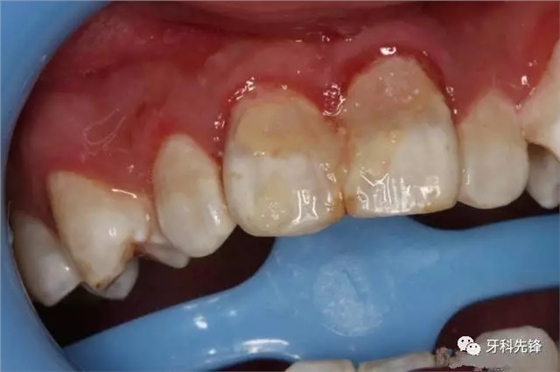

圖3.術前患者口內(nèi)像,12、11松動Ⅱ°,21松動Ⅰ°。